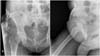

Clinical treatment with medication was given but failed to stop the progression of the calcinosis or attain remission. The patient took azathioprine and prednisone to stabilize the underlying disease and denied prior surgeries. In the physical examination, she presented with a hardened cluster of lesions adhered to the subcutaneous tissue in the inguinal region and bilateral flanks that were compatible with calcinosis and felt discomfort with light, passive movements. She showed no signs of localized infection or ulceration. The lesions covered an area of 20 × 5 cm (Figure 1). Ultrasonography of the inguinal region showed hyperechoic linear and irregular masses projecting from the subcutaneous tissue in the inferior area of the lateral abdominal wall, the largest ones being 36 mm in length, which were compatible with calcification.

The photographs show a favorable aesthetic result on the 90th postoperative day (Figure 3). The histological evaluation demonstrated no degree of malignancy in the calcifications (Figure 4). The patient is currently under follow-up care by the plastic surgery department of HU/UFSC and did not present with new calcifications in the surgical area or atrophic scars during recovery.